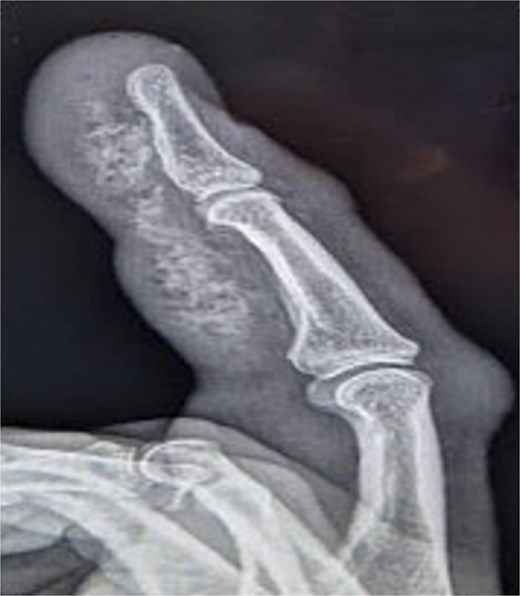

Initial presentation (Fig. 4) with accompanying X-ray (Fig. 5) and intra op image during first debridement (Fig. 6).

X-ray image of patient two showing injected material into volar surface of his digit.